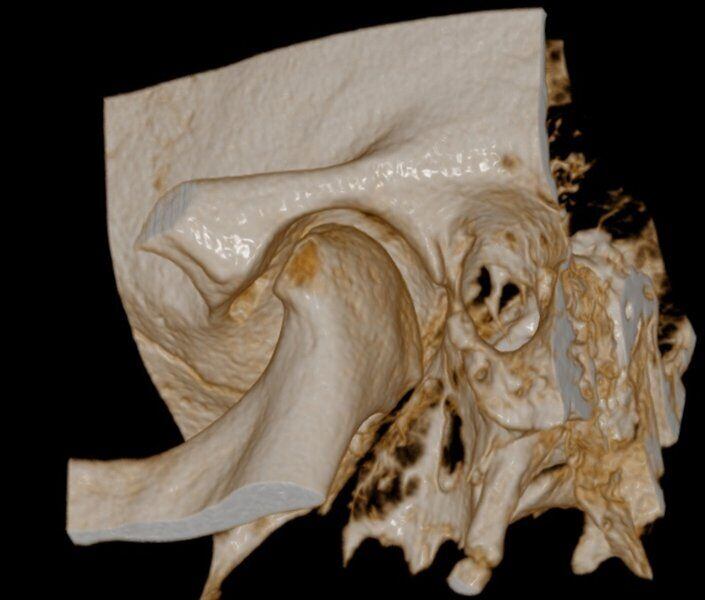

Acquisizione Maxiillofacciale per valutazione chirurgica di paziente con Sindrome di Goldenhar